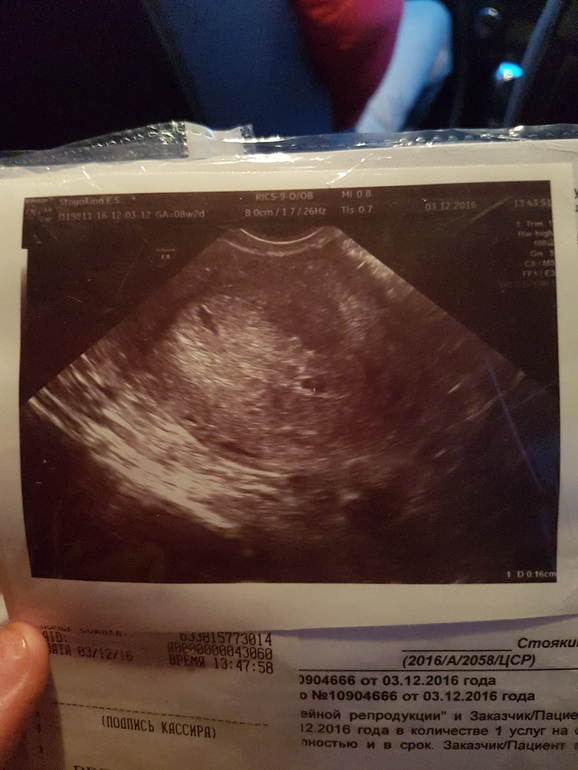

У меня тоже последние М 6.10.2016, делала узи в 5 нед и 1 день. ПЯ было в матке. Но , я точно знаю что овуляция была у меня на 14 день цикла (отслеживала по узи), и на 13 ДПО хгч был 261, узнала о беременности почти за неделю до М. Я думаю, что у вас была поздняя овуляция, наверное прям передМ. Думаю через ннедельку уже все увидят

Что-то тоже не понятно. А в ноябре не было месячных? У меня такая же точка была в 5 нед от месячных. ХГЧ было, правда, 8000. Сказали через нед повторить УЗИ -сделала через 6 дней -ктр 5 мм, сердцебиение 110 уд/мин. Мне кажется,у тебя все хорошо просто срок маленький, если оценивать не по месячным, а по хгч. Сходи через недельку -все будет ОК. Удачи!

Что-то не понятно, у вас по М скоро 9 недель? А по узи 4-5

По хгч акушерский 4,эмбриональные 2, рано еще смотреть и говорить что-то на таких сроках) сходите на узи через 2 недели)